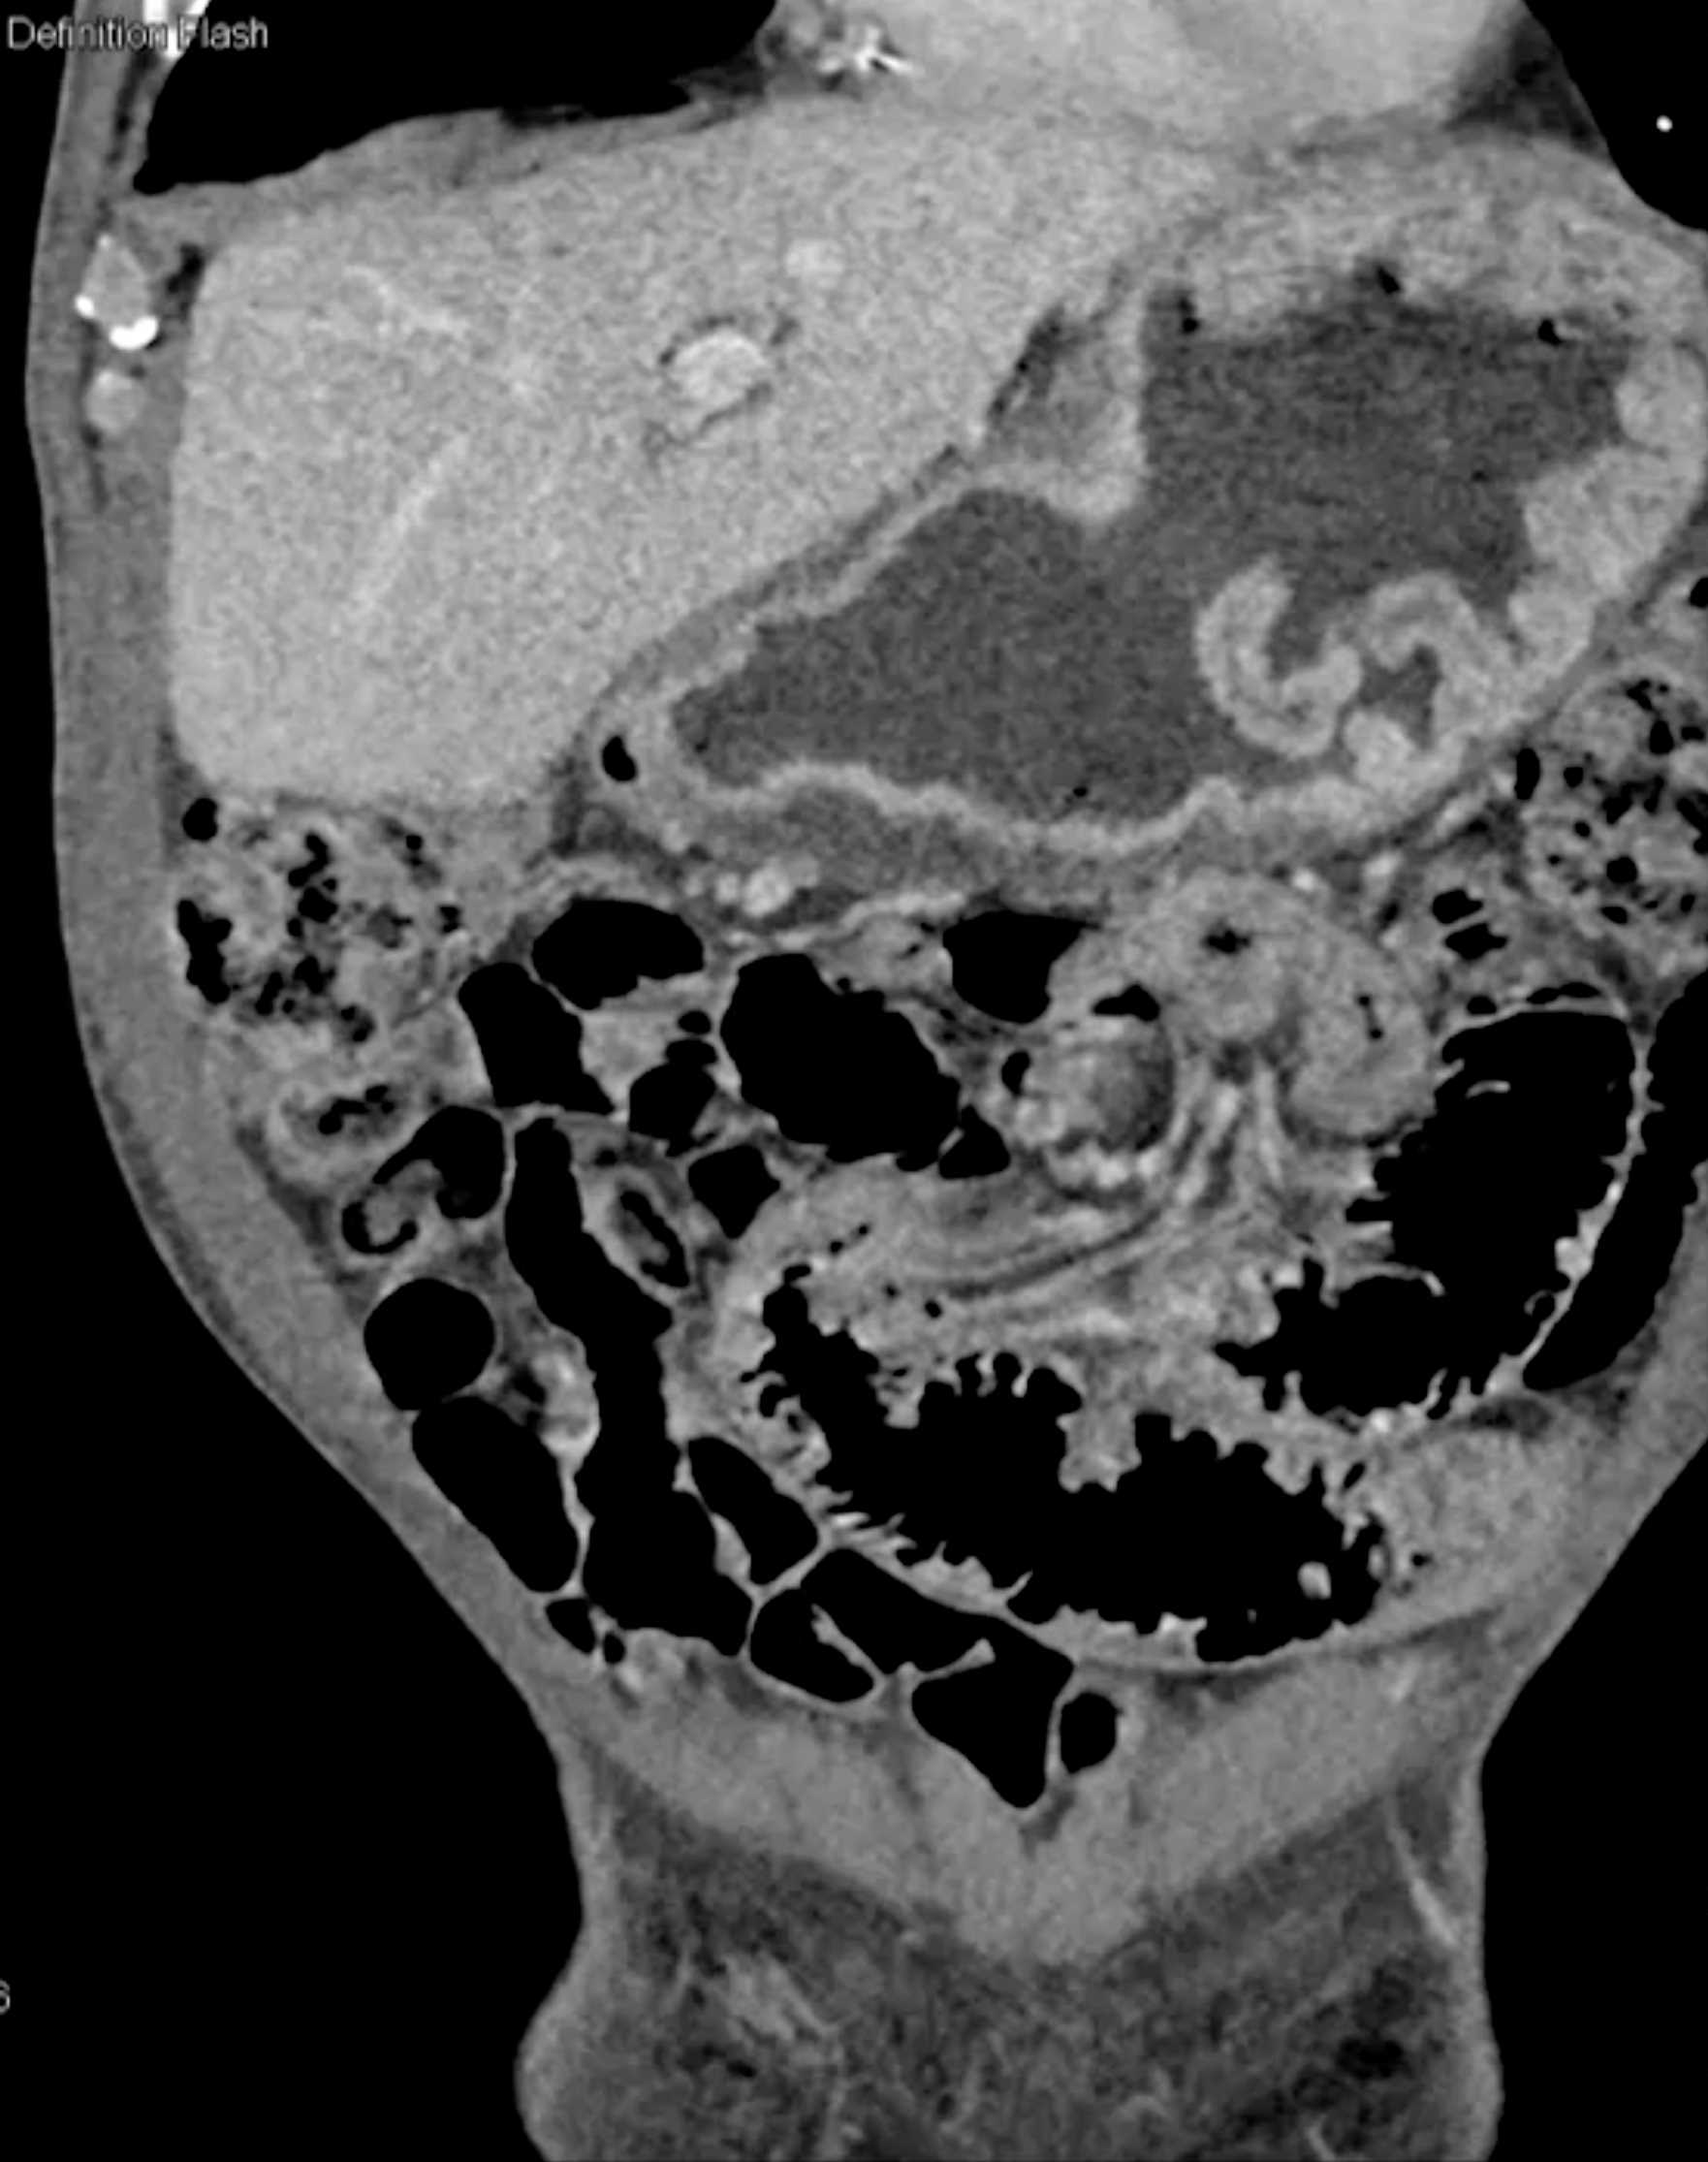

Chemical Gastritis due to NSAIDs